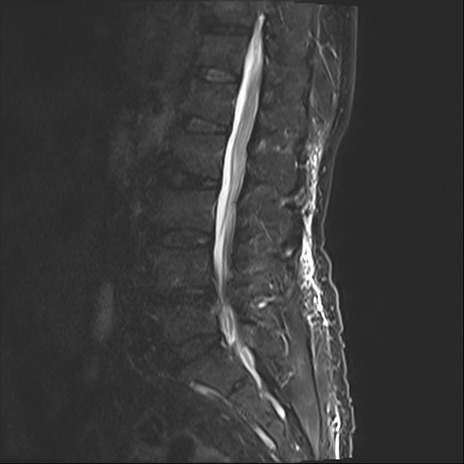

【整形】TIPS症例2 腰椎MRI STIR(矢状断像)

【症例】70歳代男性

【主訴】左下肢痛

【現病歴】2週間前くらいから腰痛、左下肢痛あり。左臀部から大腿、下腿外側のしびれが常時ある。歩行とともに同部位の痛みあり。

【身体所見】Lasegue70-/60+、Bragard-/±、PTR ±/±、ATR -/-、IP 5/5、TA 5/4、TS 5/5、EHL 右第1足趾なし/3、FHL 5/5、hypersthesia(-)、足背動脈触知良好

異常所見と診断は?